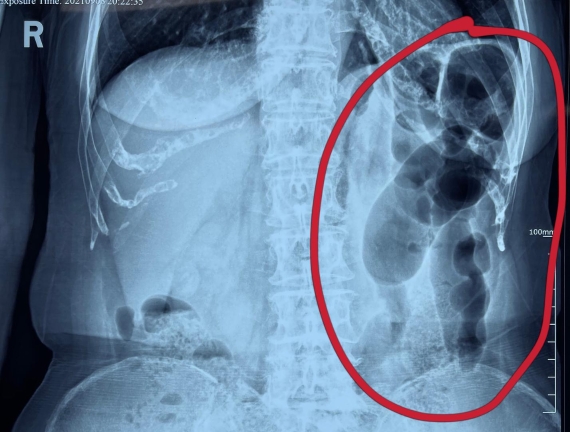

據(jù)省醫(yī)院消化病院消化二科姜子曄醫(yī)生介紹,韓大娘今年已經(jīng)73歲,家住哈爾濱市,一周前開始腹脹腹痛,有較為明顯的左側(cè)腹部疼痛,疼痛劇烈時(shí)會(huì)出現(xiàn)左側(cè)腹部鼓包情況,排氣排便后有所好轉(zhuǎn)。韓大娘家人見狀將其送到了黑龍江省醫(yī)院,門診檢查腹部平片提示為左側(cè)腹部積氣,口服全消化動(dòng)力藥及通便治療后腹痛腹脹有所緩解,入院前再次突發(fā)左側(cè)腹痛加重伴有明顯腹脹,急診隨后以“腹痛腹脹原因待查”將韓大娘收入到消化病院消化二科。

姜子曄醫(yī)生熱情接待了韓大娘,為其進(jìn)行了仔細(xì)查體,除了左側(cè)腹部壓痛并未見明顯異常,對(duì)癥給予灌腸后,韓大娘的腹脹有所緩解,第二天姜子曄醫(yī)生為韓女士進(jìn)行了胃腸鏡檢查,也未見明顯異常。但此時(shí)韓大娘腹部平片結(jié)腸腸管擴(kuò)張仍然很嚴(yán)重,腹痛腹痛也沒緩解,到底什么原因呢?消化二科主任陸以霞在查房時(shí)建議繼續(xù)給予韓大娘口服全消化動(dòng)力藥,必要時(shí)灌腸治療,同時(shí)陸以霞主任在追問病史查體時(shí)發(fā)現(xiàn)韓大娘左下腹紅色皮疹和小水泡,反復(fù)抓撓腹部皮膚部分已結(jié)痂,高度懷疑為帶狀皰疹。